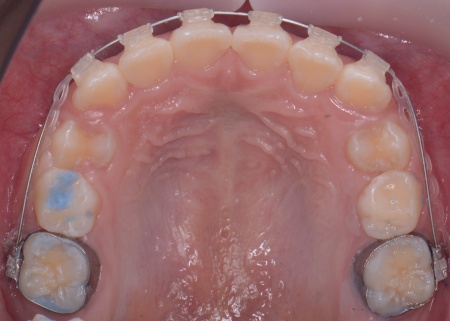

メリット デメリット また、治療にあたりお口全体のバランスを確認したところ口元の突出はなく、顎のサイズはやや小さめですが、成長期であることから歯列の拡大が可能な状態だと判断しています。 以上の内容について丁寧に説明し、治療に同意いただきました。 まず、上顎に顎の骨を広げるための固定式の矯正器具「急速拡大装置」を、下顎には歯並びの幅を広げるための「リンガルアーチ」を装着します。 次に歯の位置を整えるため、ワイヤー矯正を開始します。 最後に、歯並びが整って見た目や噛み合わせにも問題がないことを確認し、装置を取り外して第1期矯正治療を終了しました。 現在も経過観察を継続していますが、歯が元の位置に戻る後戻りも見られず、残っている乳歯から永久歯への生え変わりも順調に進んでいます。 |